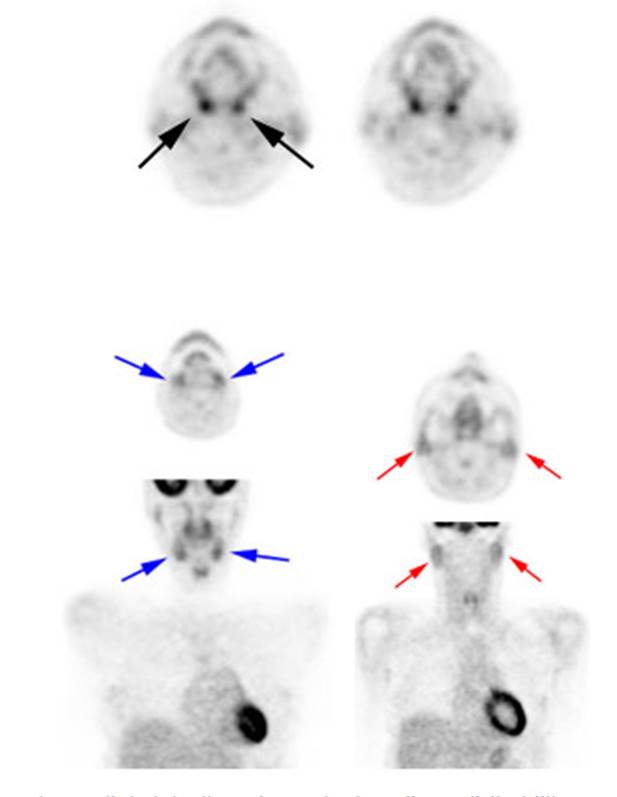

Low to moderate FDG uptake occurs in the lingual

and palatine tonsils and at the base of the tongue because of physiologic

activity associated with the lymphatic tissue in Waldeyer's

ring

Figure 3 - Head and neck activity: The images below show

typical uptake in the tonsils (black arrows),� submandibular glands (blue arrows),

and parotid glands (red arrows)